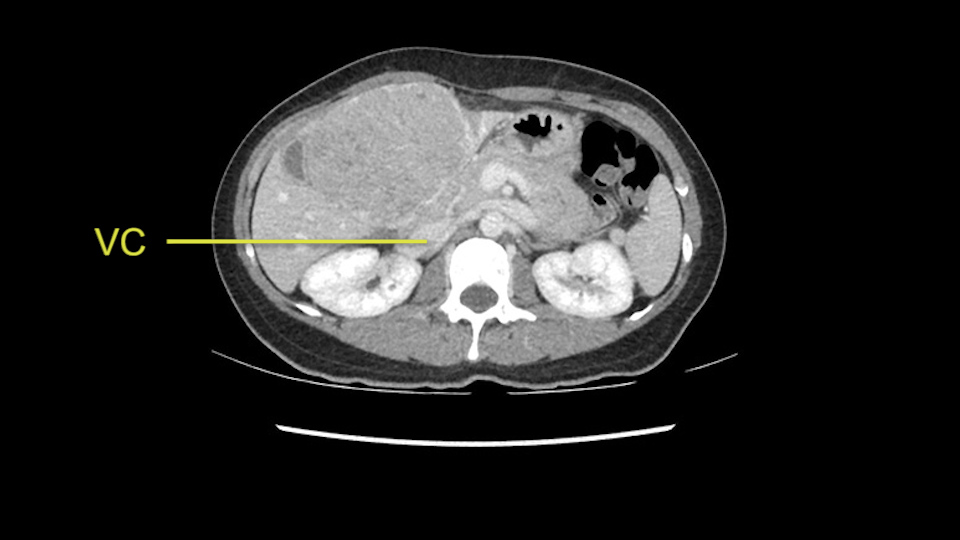

So if we look at the CT scan, on the axial, it’s a larger lesion. It’s about 6 or 7 or 8 centimeters. So it does look a bit threatening in terms of its resectability but if you really drill down deeply into the anatomy, and I think the coronal [imaging] is even better, you can see that the entire mass is on the patient’s left side of the falciform ligament. So it’s really only a left-sided tumor and not even really a left-sided tumor because Segment 4 is uninvolved anatomically.

When you see the axial sections of the scan, you find it's a largely exophytic mass and its well-encapsulated. So this is typically true of a well-differentiated hepatocellular carcinoma. If you look at this, this is the gallbladder which is being displaced to the right and the mass is in the Sg4 of the liver, exophytic, projecting down. As it is coming down, it is also displacing the duodenum and the head of the pancreas which is being pushed towards the left and it's going right up to the cava, the start of the anterior surface of the cava. Obviously getting a lot of collaterals and vascularity from all the vessels around but one has to be very careful in evaluation of the main portal pedicle in this particular case and of course arterial inflow to the Sg4 and of course the left lobe of the liver.

What kind of procedure can we plan for this patient? It obviously has to be a left hemihepatectomy because most of the lesion is actually in Sg4. Can we do something which is less than a hemihepatectomy and just do only a segmental resection? The answer to that is that this vascular supply, if you are trying to ligate only the portal venous pedicle to the Segment 4, it is very close to the tumor and you will end up not having not a great margin as far as tumor resection is concerned so I would recommend a left hemihepatectomy and not just a partial or segmental resection. You can also see that it is crossing the falciform line and going on to Segment 2 and 3 so trying to do anything less than a left hemihepatectomy may not give the right kind of margins which we need for this tumor. Fortunately for us, the contours of the liver, which are very important to see in a Hepatitis B patient, there are no cirrhosis which I can see. The normal liver functions indicate that it's a well compensated Hepatitis B.

Now let’s look at some specific anatomical points for planning this surgery. First thing you see when you see a left hemihepatectomy is that where is the left portal vein and the right portal vein branching? And what is the stump of the left portal vein available for you for ligation? In this particular case, you’ll find that there’s overhanging of the tumor but left portal vein pedicle is sufficiently available for us for ligation.

The cava however is again displaced by this well encapsulated mass, so I would expect that I should be able to lift out of the cava with some moment of careful dissection and the cava is not infiltrated by this tumor. Most of the tumor is below the portal plane and the hepatic-venous vein is completely free. You have the left and the middle hepatic vein joining together and opening up. The right hepatic vein is as usual. All the superior segments of the liver are intact so we do not expect any major problem in this particular case as far as the venous outflow is concerned. So this is about the preoperative planning as far as this case is concerned.